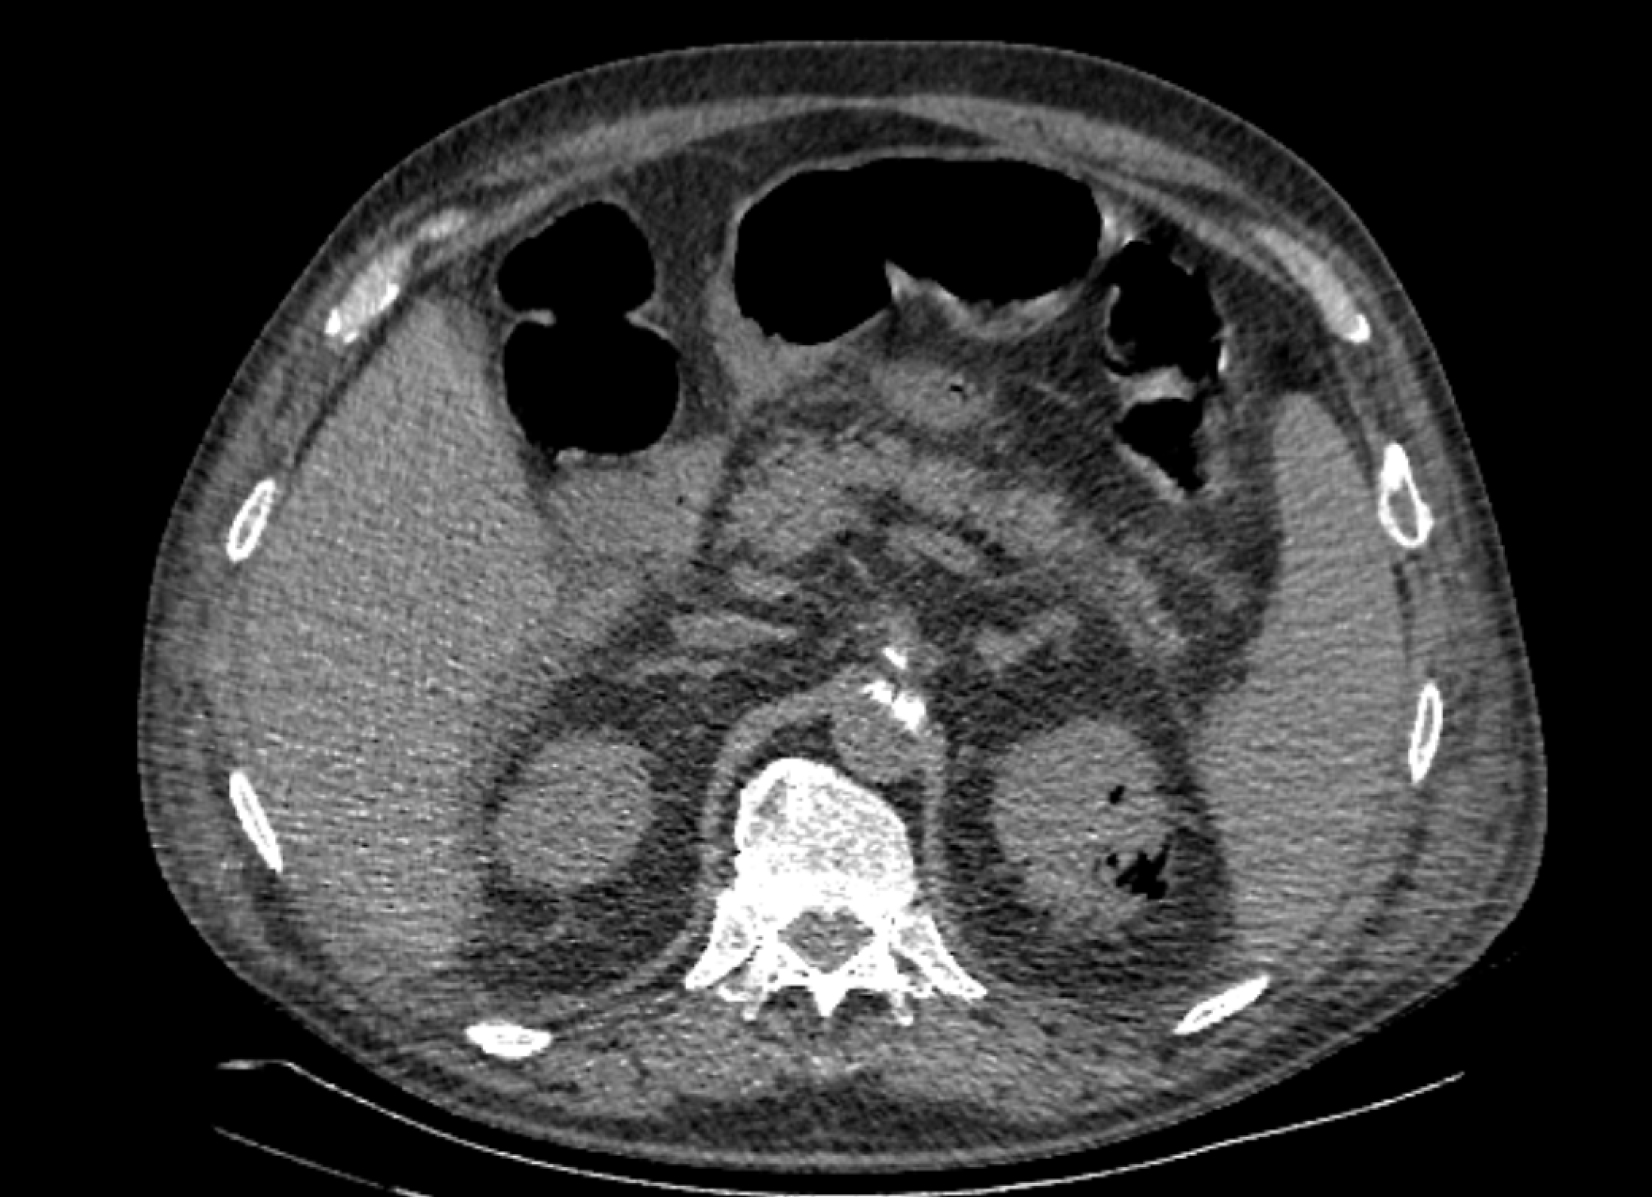

На следующий день состояние пациента оставалось тяжелым, с отрицательной динамикой, креатинин сыворотки возрос до 735,2 ммоль/л, Появились жалобы на слабость, тошноту. При осмотре: живот мягкий, вздут по всем отделам, при пальпации болезненный. Область почек не изменена, при пальпации безболезненна, патологических изменений в области почек не выявлено. Симптом поколачивания отрицательный билатерально. При УЗИ были обнаружены плевральный выпот по 300–400 мл с каждой стороны, гепатомегалия, увеличение размеров селезенки, асцит. Кроме того, в обеих почках были визуализированы тени, характерные для конкрементов. По данным компьютерной томографии (КТ) конкрементов не обнаружено, но в лоханке, на всем протяжении левого мочеточника и, частично, в правом мочеточнике, а также в мочевом пузыре визуализировался газ (рис. 1–6).

Рис. 1. Компьютерная томография органов брюшной полости, забрюшинного пространства, органов малого таза. Газ в мочевом пузыре

Рис. 2. Компьютерная томография органов брюшной полости, забрюшинного пространства, органов малого таза. Газ в мочевом пузыре